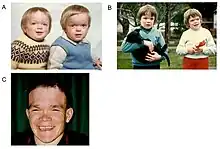

The first decade of life is characterised by the development of hearing impairment, psychomotor delay, recurrent infections, especially upper airway infections, pulmonary infections and acute/serous otitis media infections.[7] Significant changes in a number of facial features may occur, such as: protruding forehead; flattened nasal bridge; small nose; wide mouth; and widely spaced teeth.[2] Muscular weakness or spinal abnormalities can occur due to the build-up of storage materials in the muscle.[2]

Alpha Mannosidosis is a progressive disorder, and its presence should be suspected in patients with cognitive disabilities, skeletal changes (e.g. swollen joints, curved spine), hearing loss and recurrent infections. Although children with the condition are often born seemingly normal, their condition deteriorates with age. Alpha-mannosidosis can impact on a patient's quality of life in many ways, including their ability to live independently, socialise or find employment.[2][7]